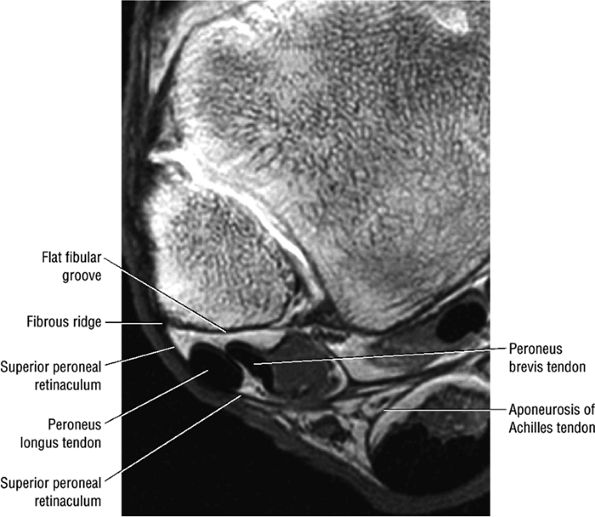

-

Bone marrow edema at the distal fibular or talar insertion

Fluid in tibiotalar effusion and adjacent tendon sheaths (peronea l tendons)